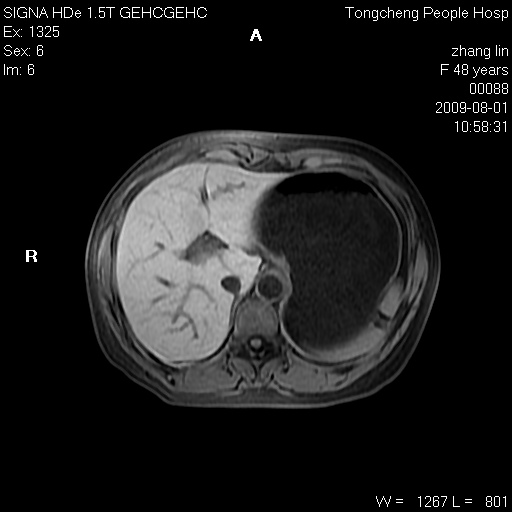

女,48岁。健康体检,彩超发现右肾占位性病变。平素健康。

临床诊断:右肾占位性病变,性质待定(囊肿?肿瘤?)。

上中腹部mr平扫+增强扫描,图像如下:

右肾上极见一类圆形病灶,t1wi呈等信号t2wi呈等高混杂信号,三期增强无强化,边界清---考虑囊肿出血。

同反相位均表现为等信号,病变无强化,考虑含蛋白的囊肿可能,弥散加权相或许有些帮助,

慢性胆囊炎